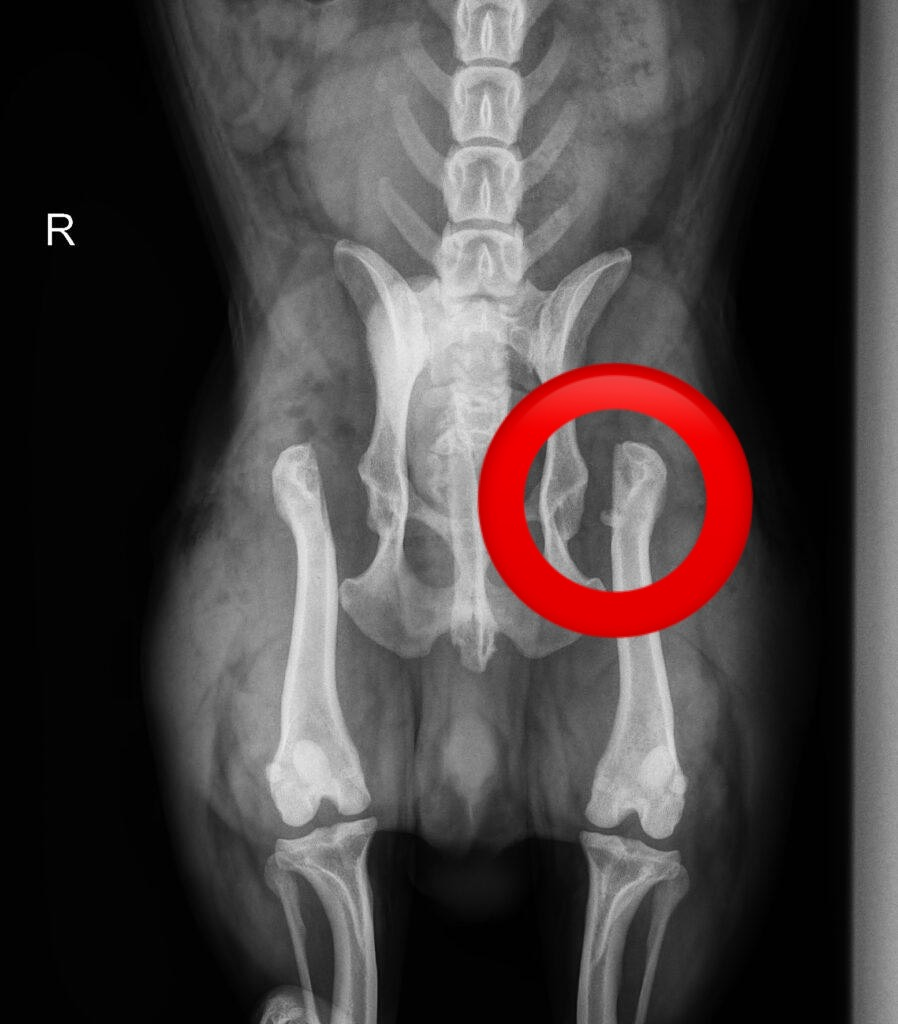

検査を進めていくと実は両方の股関節が脱臼していました。

股関節は、「骨盤側の寛骨臼」と「大腿骨の骨頭」がボールとポケットのようにはまり込んで構成されています。この構造があるからこそ、スムーズな歩行や走行が可能なのです。

しかし、この連結部分が外れてしまうことを股関節脱臼(こかんせつだっきゅう)と呼びます。